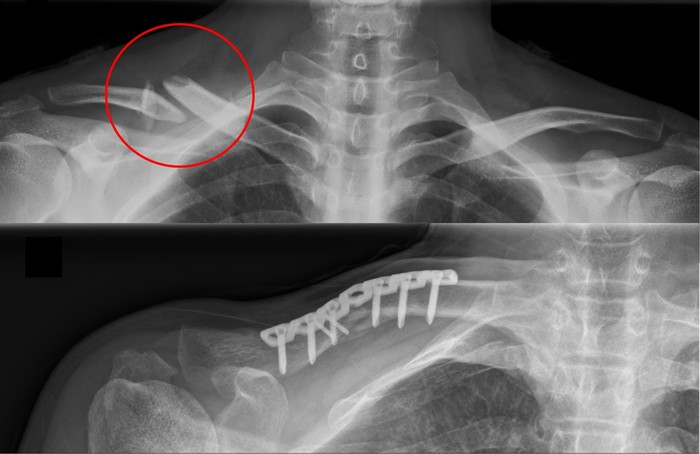

쇄골 골절은 대부분 특별한 교정이 필요하지 않는다. 팔자 붕대를 이용해 어깨 주위를 감아서 골절 부위가 안정되도록 고정한다. 대개 소아는 3~4주, 성인은 6~8주 정도 고정한다. 이후 어깨 관절의 운동 범위 및 강도를 회복시켜주는 재활 치료를 진행한다. 골절 부위가 불안정하여 유합이 이루어지지 않을 가능성이 높은 경우, 개방성 골절, 신경 및 혈관 손상이 동반된 경우에는 수술적 치료를 시행할 수 있다. 수술에서는 골절 부위를 고정하기 위해 금속 핀, 나사, 금속판 등을 사용한다.

(위) 쇄골 골절의 x-ray 소견 (아래) 수술 (금속판 고정술) 이후의 모습